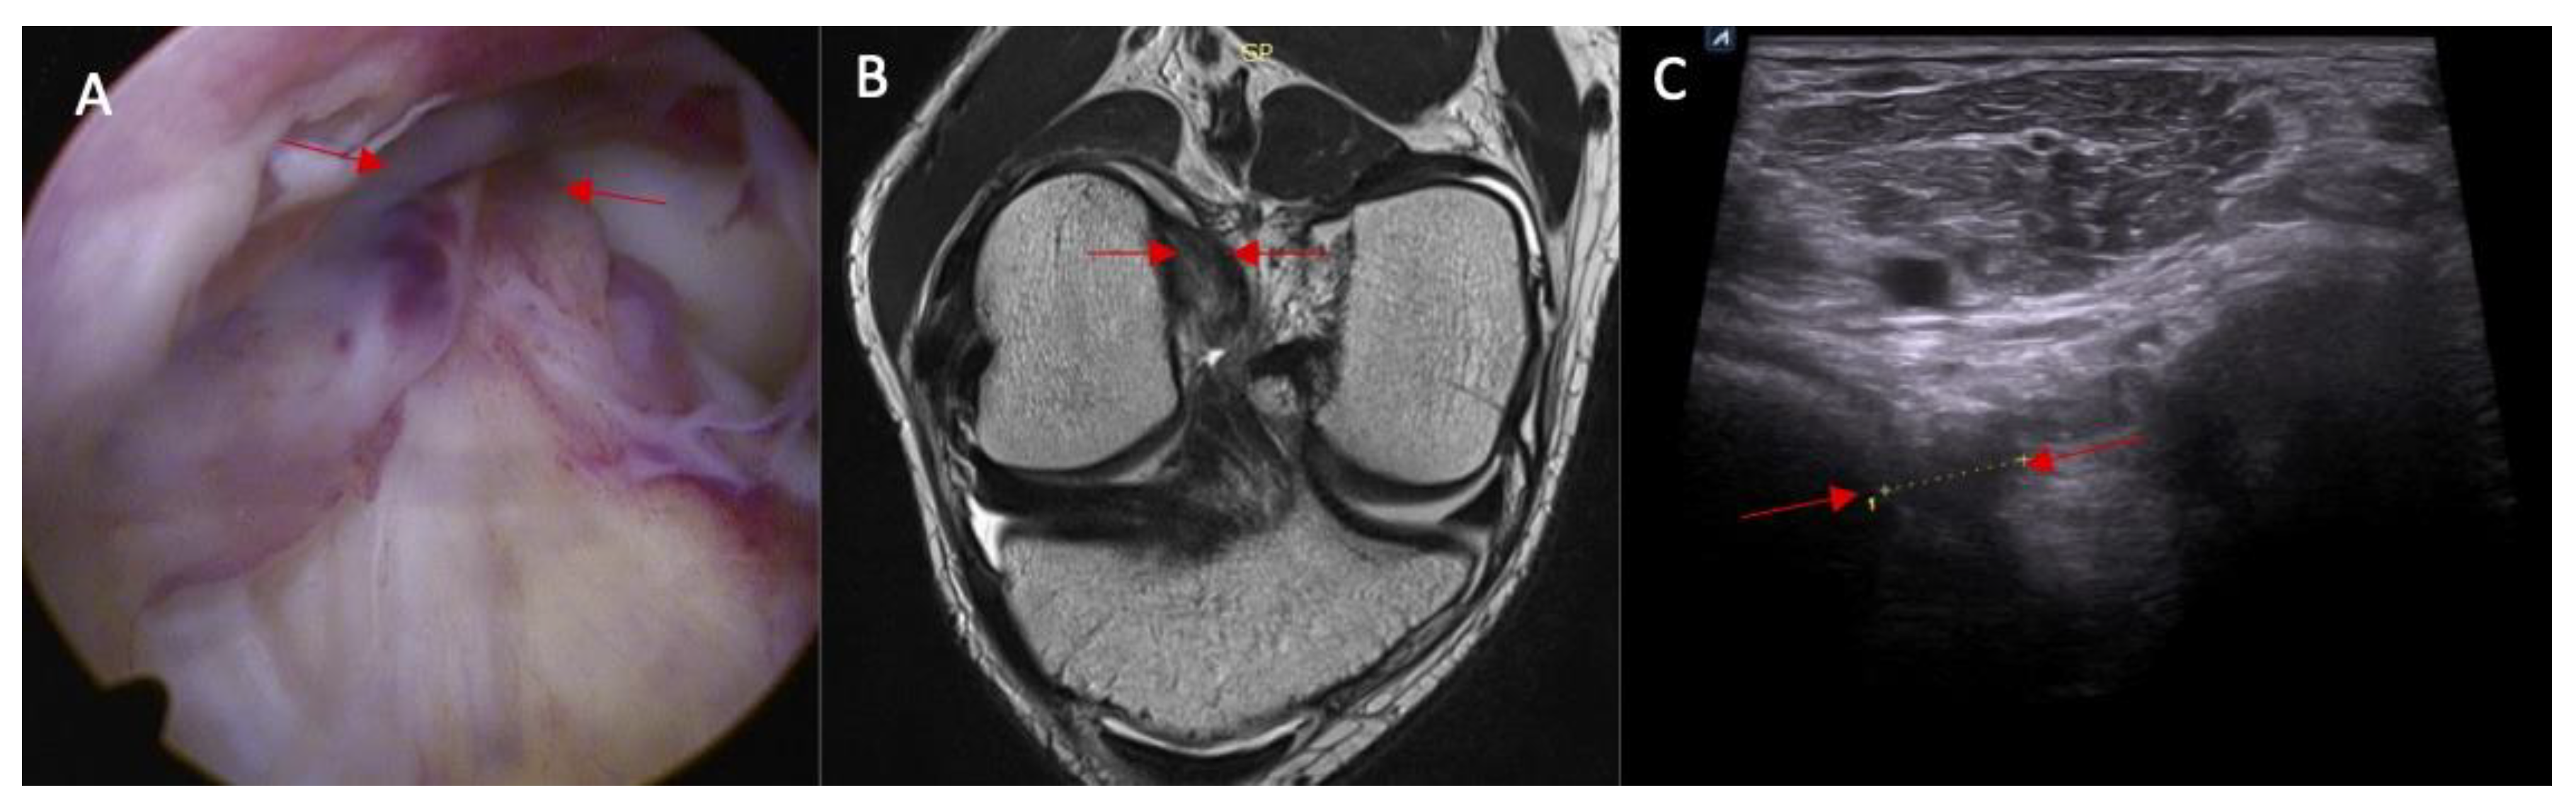

- Swelling/scarifications of the ACL/posterior crucial ligament (PCL) with change of the morphology of the posterior joint capsule complex—the patient is in prone position with knee full extension. The transducer is applied parallel to the long axis of the lower limb.

2.1. Part I—Anatomical Study

3.1. Part I—Anatomical Study